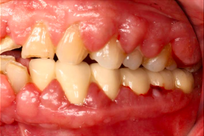

Case Background

A 65-year-old female on antihypertensives and immunosuppressants presented with severe gum swelling, inability to chew, and difficulty maintaining oral hygiene. This led to multiple decayed and periodontally compromised teeth, worsening her overall condition.

Drug-influenced gingival overgrowth or ‘DIGO’ in short, manifests as abnormal swelling of the gingiva.

- The condition is usually caused by adverse reactions to certain drugs such as antihypertensives, anticonvulsants or immunosuppressants.

- As the gum tissues become significantly larger, it may impede normal masticatory function, daily oral hygiene, and aesthetics, severely diminishing one’s quality of life. (Sabarudin et al. 2022)

Before Treatment